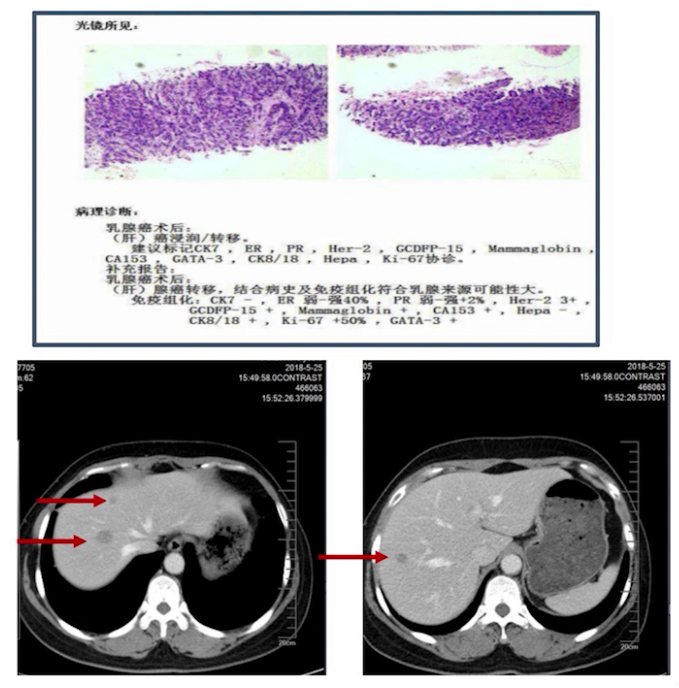

2018年5月11日超声提示肝脏占位;22日行肝脏肿物穿刺病理提示转移癌,结合病史及免疫组化考虑乳腺来源,ER 40%,PR 2%,Her2(+++),Ki-67 50%;上腹部CT提示肝脏多发低密度结节,考虑转移,其余相关检查未见异常。

经与患者沟通,患者要求参加临床研究。2018年6月-2019年6月行多西他赛联合曲妥珠单抗或HLX02治疗9个周期,后续行单药靶向药物维持治疗8个周期,疗效评价PFS期13个月;上腹部CT提示两周期后肝脏病灶明显缩小,达PR状态。